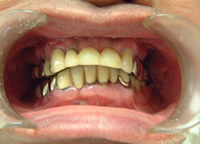

症例7 53歳 男性 NEW

上3本 下3本 本人の歯を残した症例

治療前

治療後

当医院にてインプラント20本埋入